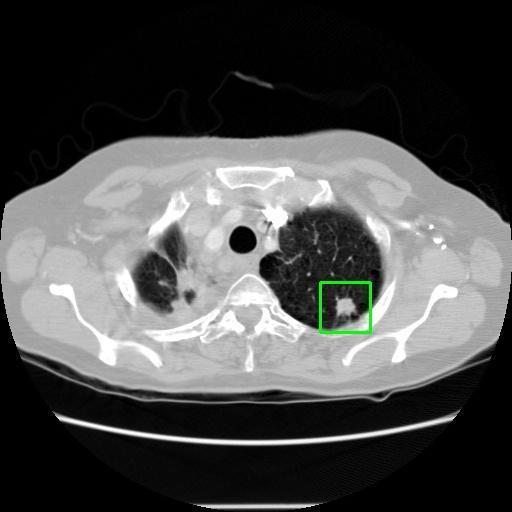

We developed an AI-based system using deep learning models for analyzing lung CT scans to detect and classify pulmonary nodules. We chose the YOLOv11 architecture for its enhanced object detection capability and adapted it specifically for medical imaging, incorporating pixel-level precision and severity classification.

Classification into three severity levels with colored bounding boxes.

Successfully built and deployed an AI model (YOLOv11) capable of detecting lung nodules in CT scans with high accuracy and real-time performance.

Designed a severity classification system that categorizes nodules into null, moderate, and severe using colored bounding boxes, assisting in rapid clinical decision-making.